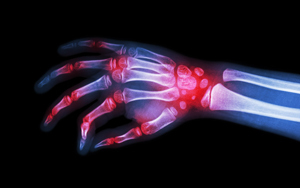

Biosimilars bear out need for FDA’s clarification

Two high-cost arthritis medications — one the world’s best-selling drug — may soon make way for generic equivalents following preliminary committee approval, but the Food and Drug Administration must still decide whether the products are fully interchangeable. Read More »

FDA advisory panel recommends biosimilar version of Humira

An advisory panel of the Federal Drug Administration (FDA) recently recommended approval of a medication manufactured by Amgen as a feasible alternative product to Humira, a brand created by AbbVie. Read More »